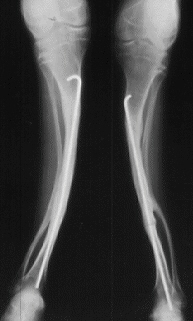

A 20-year-old -male. Body height 145cm. Sillence type I.

The first visit was 3 years of age. He sustained 12 fractures in L/E and underwent 16 operations. He had no scoliosis. Initial gate was obtained when he was 18 months old. He had been a practical ambulator until 16 years old. He can walk 100m on crutches, however, he rather depends upon a wheelchair after he went to high school because of a fear of fractures and convenience for quick transportation. The diameter of the femur has been over 10 mm since 3 years old and is 17 mm now.